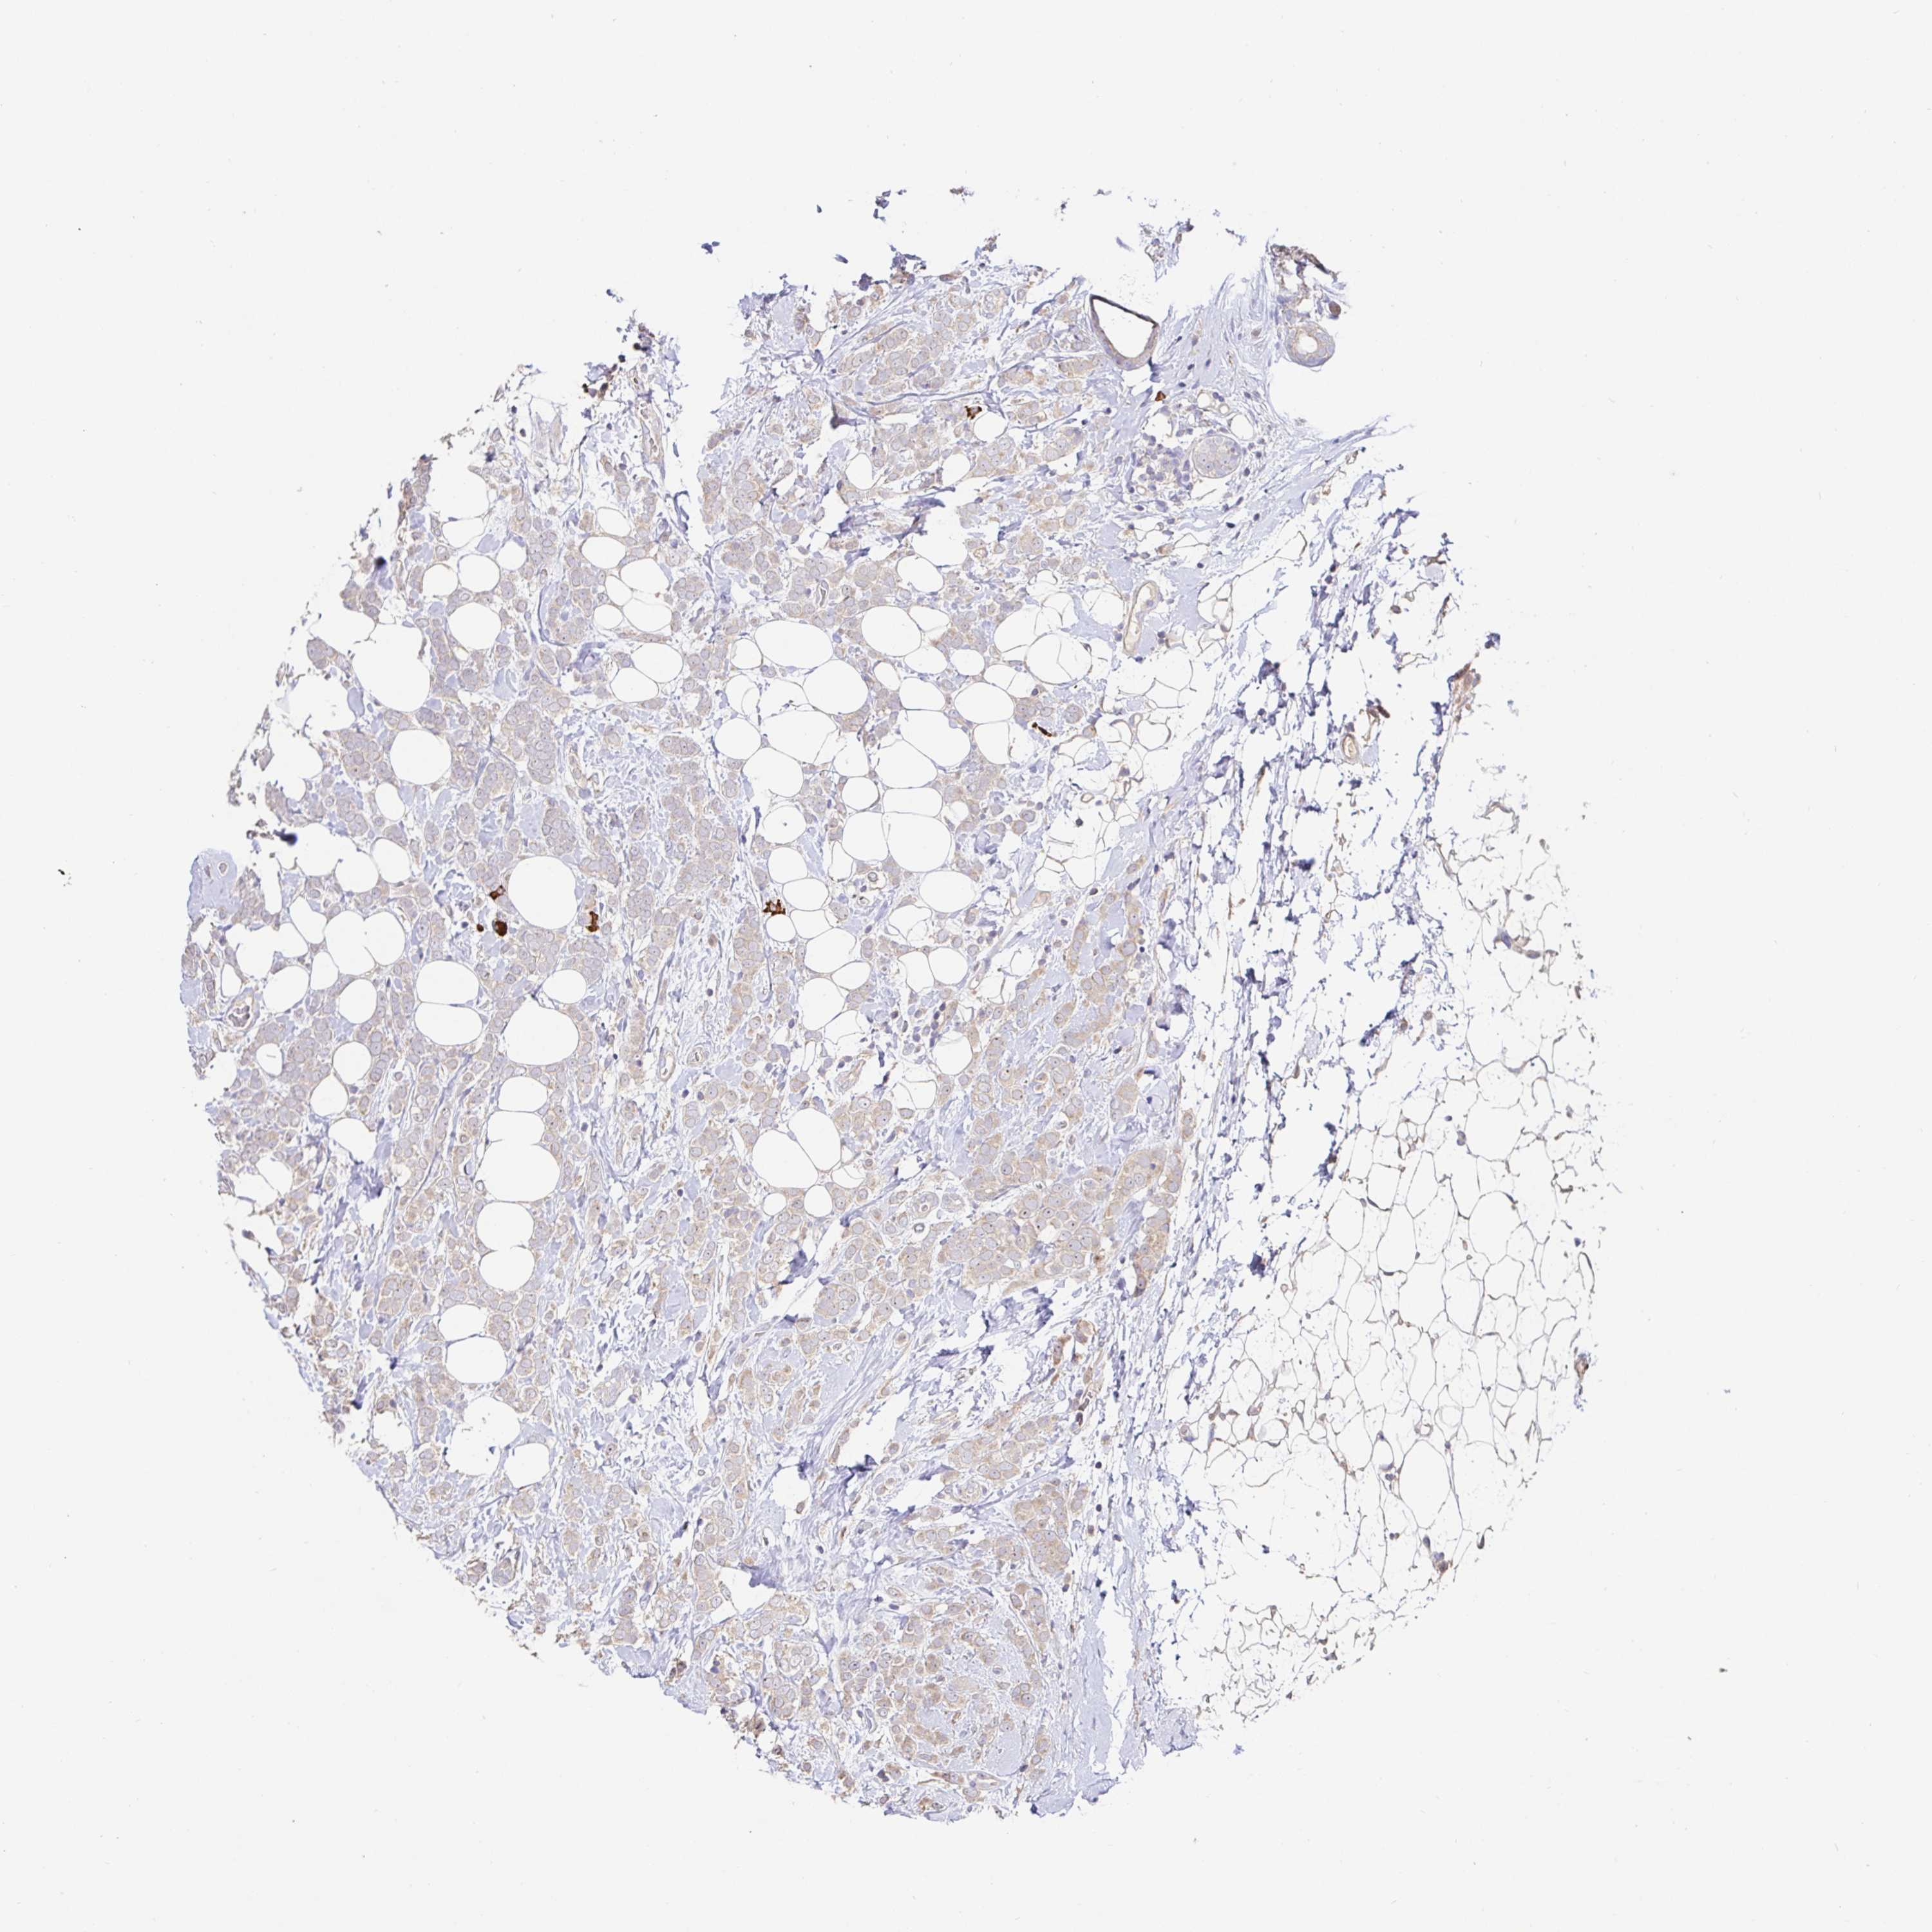

CANCER BREAST CANCER Show tissue menu

BRCA TCGA BRCA VALIDATION PROTEIN EXPRESSION